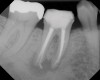

Figure 4  Clinical case of a lack of coronal seal that contributed to the failure of this root canal treatment.

Figure 4

Figure 5  Retreatment of the case shown in Figure 4.

Figure 5